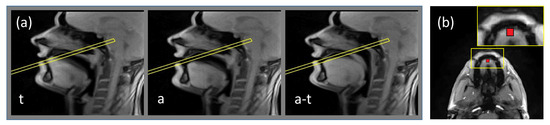

In order to define the slice position for the phase-contast sequence, all images of the series acquired in the mid-sagittal plane of the subject articulated /tata/ were displayed on the scanner console, and the slice for the phase contrast sequence was chosen to be touching the hard palate and perpendicular to the tongue motion direction. During the acquisition with the phase contrast sequences, the subject was articulating the same utterance /tata/ at the same rate and articulation. The resulting dynamic series was used for determination of the region of interest (ROI) corresponding to the tongue tip, which was chosen to be a 5 × 5 pixel square (5.6 × 5.6 mm2. Examples of the slice position and of the region of interest are shown in Figure 1.

Figure 1. Illustration of the routine of the slice and region of interest positioning. (a) examples of frames of dynamic acquisition of the subject obtained with the real-time MRI sequence in the mid-sagittal plane: during production of /a/, of /t/ and transition between /a/ and /t/. The frame denotes the position of the slice touching the hard palate and perpendicular to the tongue motion direction; (b) example frame of the acquisition in the plane denoted by the frame in Figure 1a. Region of interest is shown by the rectangle. The inset presents zoomed-in region containing ROI.